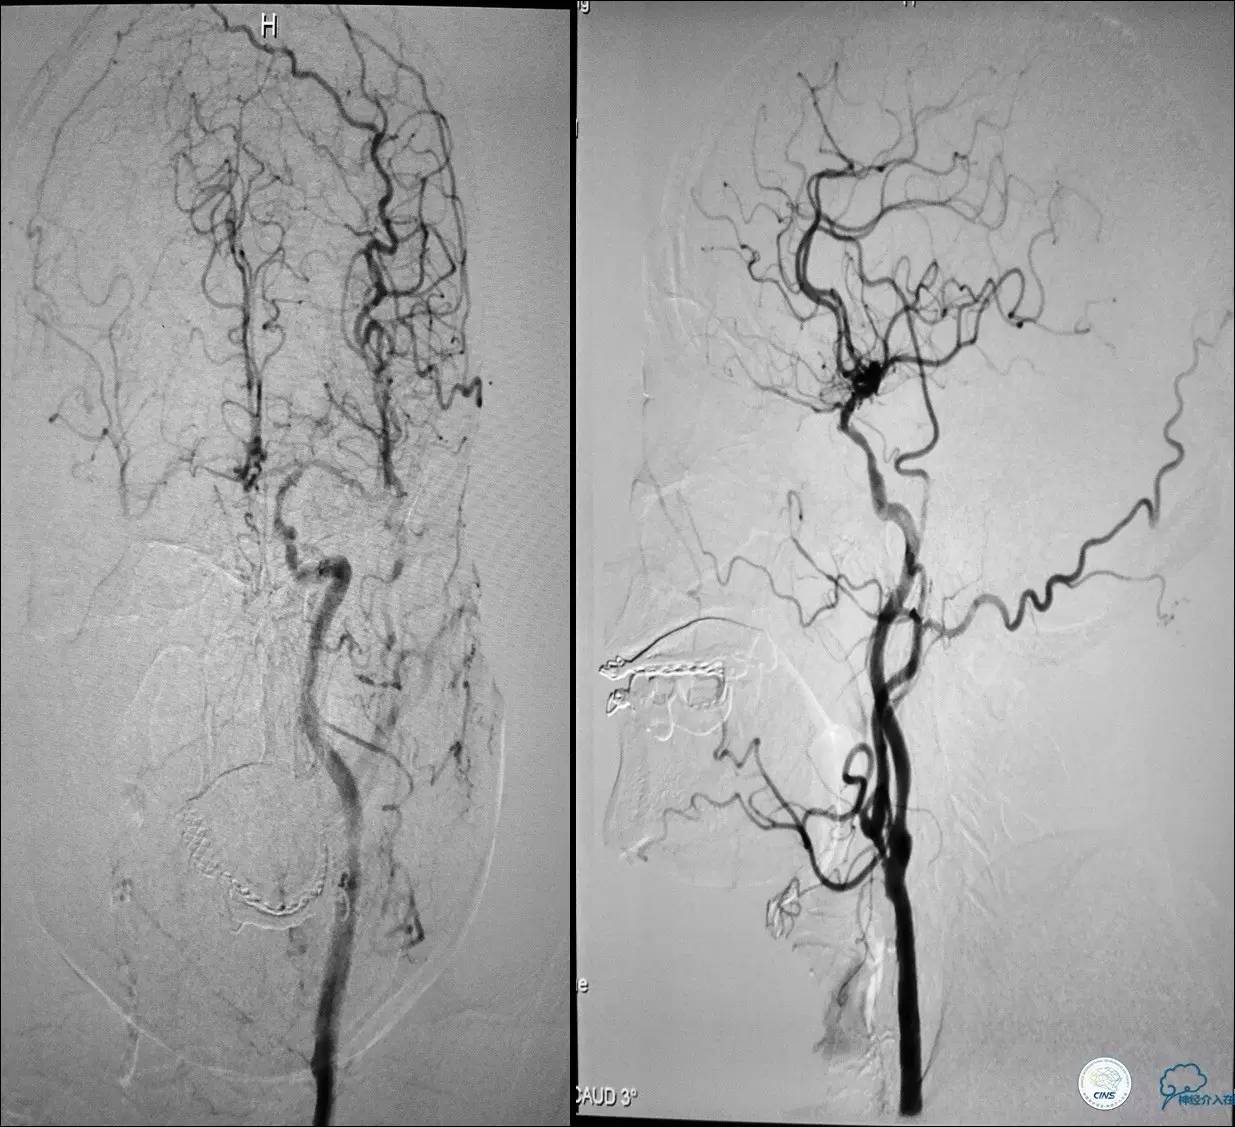

颈动脉次全闭塞 术前评估

》头颅灌注+DSA!

头颅灌注: 注意两侧CBF CBV的对比。

DSA:注意侧支代偿。

术中技巧

》当成颈动脉闭塞开通做,同时8F鞘内套以4F鞘给予微导管足够支撑力。

》避免后扩,分次治疗。

》术中脑保护,首选SPIDER。

★脑保护技术:病死率及卒中率从7.9%~9.1%降至1.7%,已作为CAS治疗常规。